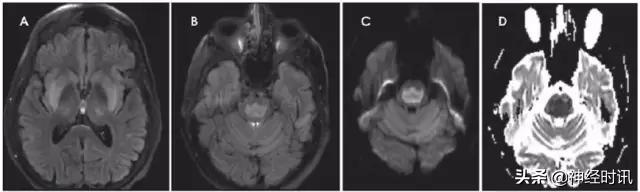

Wernicke脑病见于伴硫胺素缺乏的嗜酒和其它营养不良患者。患者出现精神状态改变、记忆损伤、眼肌麻痹或共济失调。典型MRI显示乳头体、下丘脑、内侧丘脑、顶盖和导水管周围区域对称性T2/FLAIR高信号,大脑皮质也可能受累。在疾病早期,可见到由于细胞源性水肿导致的弥散受限(图8)。

图8 一例62岁女性,复视3个月,听力丧失数天,因眩晕、恶心、呕吐、眼震和厌食来诊。她被诊断为营养缺乏导致的Wernicke病,硫胺素水平为35 nmol/L (正常70–180)。MRI显示四叠体板、中脑导水管周围灰质、下丘脑和双侧上丘FLAIR高信号和各种不同程度的弥散(A:DWI,B:ADC)。